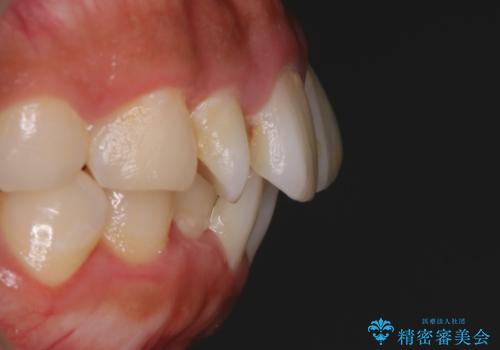

顔貌写真でも明らかに口の閉じやすさやEラインが改善している様子が分かります。

インビザラインで口元の変化

一般的に口元を下げるための治療というと抜歯矯正を思い浮かべる方が多いかと思います。そもそもガタつきを治したり歯を引っ込めるためのスペースの作り方には大きく分けて4種類の方法があります。

①抜歯 ②歯列の幅の拡大 ③IPR(歯の幅を削って小さくする) ④歯の後方移動 です。

インビザラインの登場により抜歯以外の3種類の方法を効率よく活用することができるようになりました。

そのため、非抜歯でも口元の環境が改善するケースがあります。